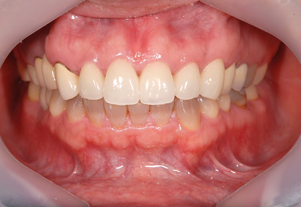

ジルコニアクラウン

金属と同じ強度を持ち、生体親和性の高い

安全かつ美しさを兼ね備えた素材です。

人工ダイアモンドと呼ばれるジルコニアは、金属を使用していないため金属アレルギーをお持ちの方でも安心してご使用いただけます。従来の金属に比べ約1/3の軽さで自然な噛み心地を体感していただけます。

Before

After